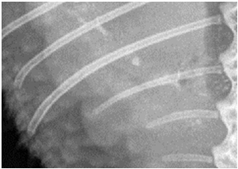

![]() | Left last rib: assessability of cancellous bone and cortical bone along the bone:demarcability of cancellous bone to cortical bone, demarcability of structures to surrounding area. |